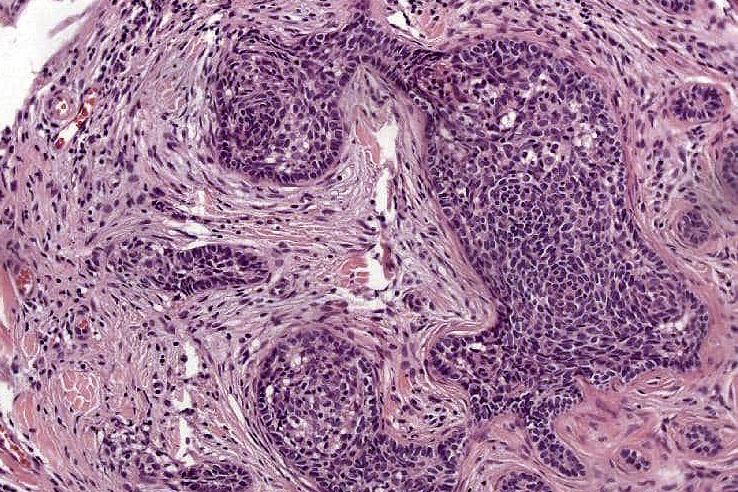

•Dermal nodule, rarely extends into subcutaneous fat

•Irregular lobules of epithelial cells embedded in a dense fibrous stroma

•Peripheral rim of darkly staining basaloid cells surrounding larger pale staining cells with vesicular nuclei with often prominent eosinophilic nucleoli

•Admixed lymphocytes (an obligatory feature)

•Germinal centers sometimes present

•+/- focal sebaceous differentiation (rare)

•+/- focal ductal differentiation (rare)